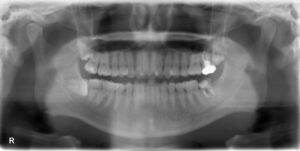

下顎オールオン6症例

BEFORE AFTER 78歳女性/下顎6本 【治療内容】 下の歯が、骨吸収により全体的に揺れている状態で来院された患…